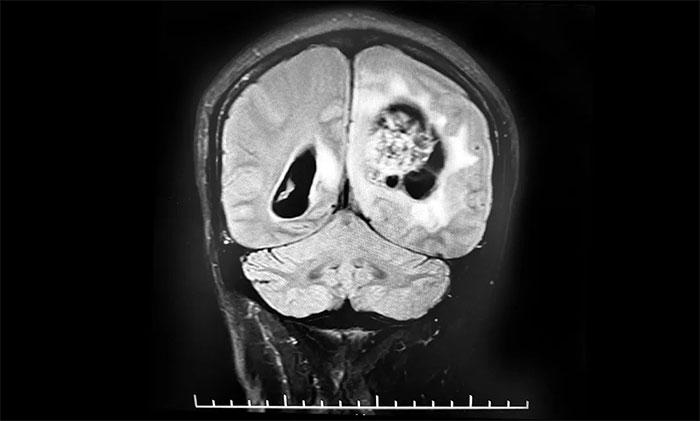

脑胶质瘤影像学及鉴别诊断 - 美篇